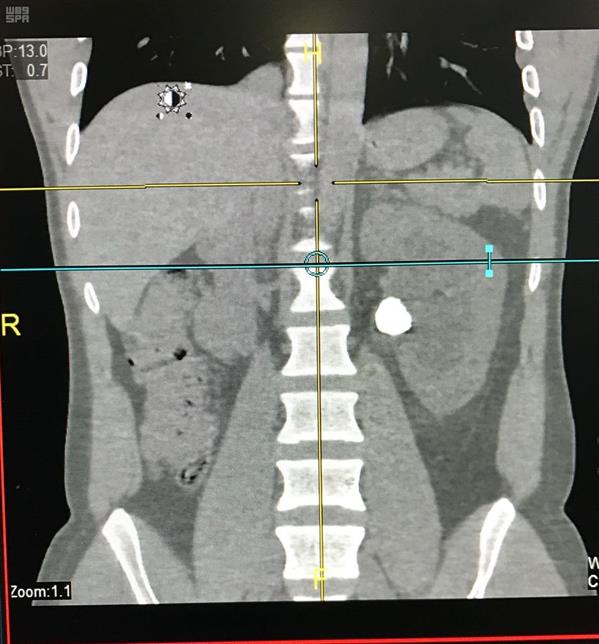

نجح فريق طبي بمجمع الملك فيصل الطبي في إجراء أول منظار لاستخراج حصوات الكلية عن طريق فتحه صغيره لاتتعدى السنتيمتر الواحد في جسم المريض .

ونجح الفريق بقسم المسالك البولية بالمجمع برئاسة الدكتور أشرف اسعد سليمان استشاري المسالك البولية في إجراء عملية منظار دقيقة وتكسير الحصوة واستخراجها بالكامل لمريض عشريني بعد أن تعرض للمعاناة طويلاً في عدم قدرة المريض على العمل حيث نجح الفريق في إنهاء معاناة المريض .ويتمتع المريض بصحة جيدة ولله الحمد .